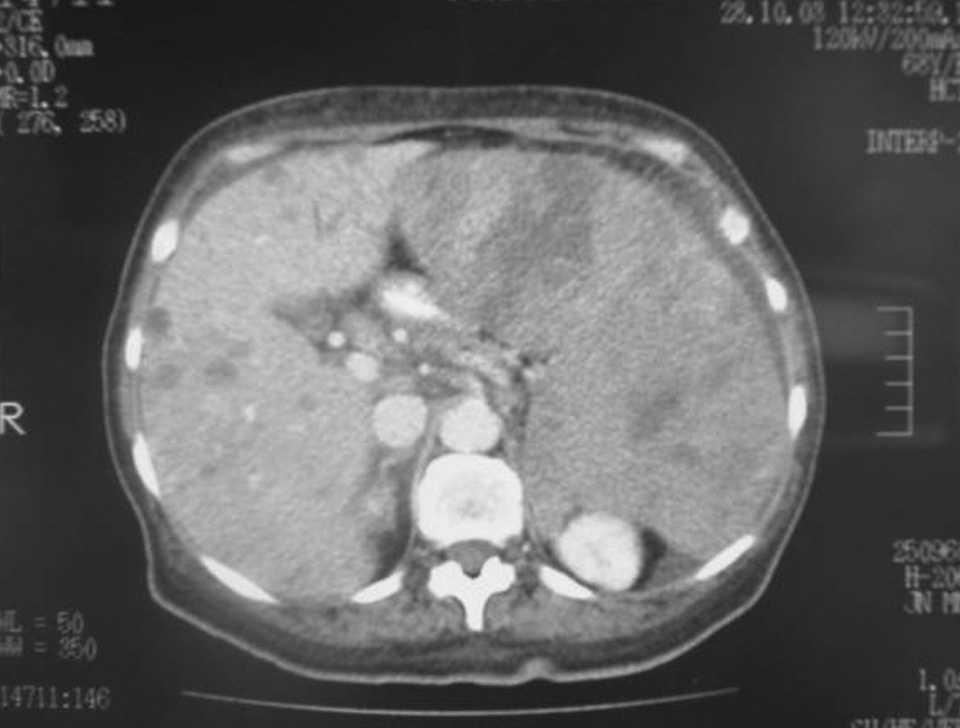

Mujer de 68 años de edad, sin antecedentes de interés, que consulta en junio de 2003 por un cuadro de anemia ferropénica no filiada desde hacía unos 2 meses, tratada mediante hierro oral, cambio de ritmo deposicional, discreto síndrome tóxico con pérdida de unos 3-4 kg y discreta molestia abdominal en la zona epigástrica. En la exploración física presenta fiebre de 38 oC, una tumoración dura, bien delimitada, que ocupa la mayor parte del epigastrio y el mesogastrio, así como una hepatomegalia de 2 traveses. Analíticamente sólo destaca una anemia. La primera exploración fue una colonoscopia que informó de una compresión externa del colon descendente sin evidencia de infiltración. La TC informó de una esplenomegalia gigante y una hepatomegalia, ambas con múltiples lesiones hipointensas e isointensas, algunas con captación anular, de morfología redondeada pero en el bazo bastante cuneiformes.

Fig. 1. Tomografía computarizada con contraste intravenoso (fase portal). Hepatomegalia con múltiples lesiones hipointensas, algunas con captación anular, y esplenomegalia con múltiples lesiones hipointensas mal definidas, algunas cuneiformes.